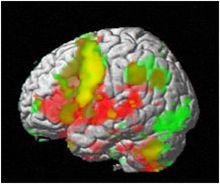

研究

fMRI研究腦功能網路fMRI的方法是非介入性的,所以套用此方法既可以對單一受試者進行多項研究,也可以對經科學分組的群體進行橫向研究。和其他非手術腦功能定位技術(如PET、EEG 、MEG及近紅外光譜儀成像)相比fMRI具有非常好的空間解析度和時間解析度。這些特性為對人腦進行多種新穎的認知神經科學的實驗提供了有利條件,並可進行腦病理的研究,具有相當大的臨床意義。

套用fMRI對執行一組相同任務的受試群組的皮層活動模式進行比較還不多,但類似的工作不難開展。迄今為止較成功的研究有: 癲癇病人和正常人的語言偏向的研究; 先天耳聾者和正常聽力人群的參與閱讀英語和美國手語的大腦區域的比較。今後可能的研究方向包括認知的交叉文化的研究(從與閱讀不同文字元號有關的皮層區域開始)、非語言推理的速度和皮層活動的定位及區域大小之間的關係。將fMRI數據標準化至一個共同的立體空間(比如Talairach空間)的能力允許把顯著性的活動投入共同的標準空間中加以分析 和比較。